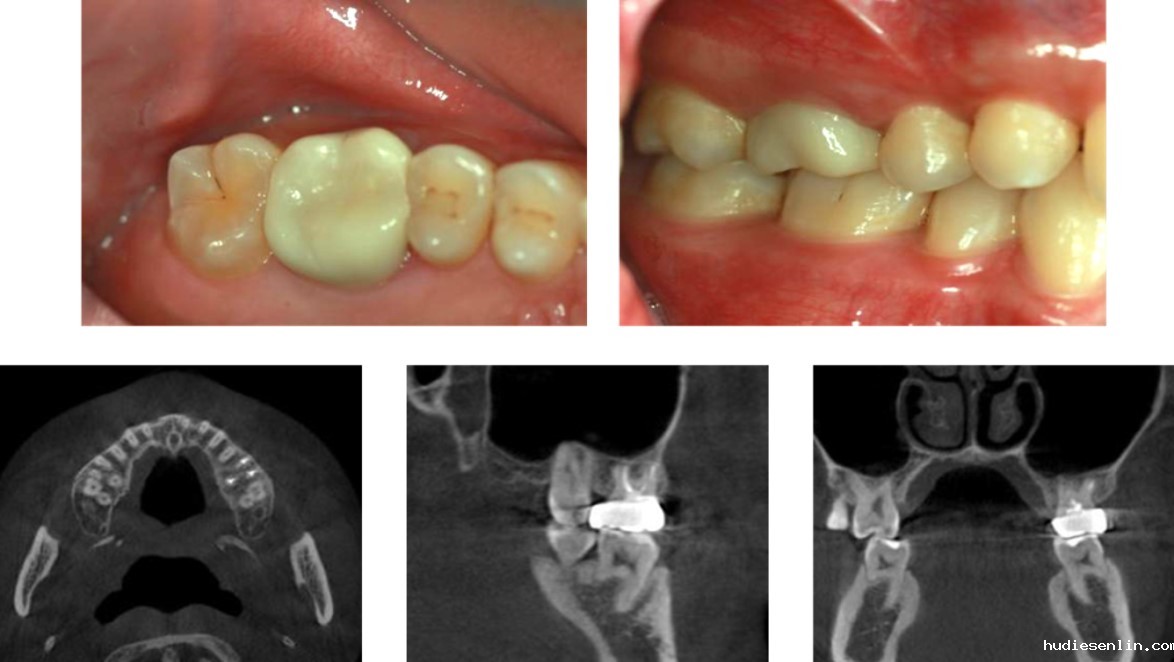

1. 术前准备:通过CT精准定位病变范围,制定个性化方案。